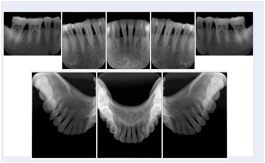

Intra-oral radiography typically involves acquisition of multiple images of various parts of the dentition. Many digital radiographic systems offer customized templates that are used for displaying the images in a study on the screen. These templates may also be referred to as mounts or view sets. The Structured Display Object represents a standard method of encoding and exchanging the layout and intended display of Structured Displays. A structured display object created in this manner could be stored with a study and exchanged with images to allow for complete reproduction of the original exam.

1. A patient visits a General Dentist where a Full Mouth Series Exam with 18 images is acquired. The dentist observes severe bone loss and refers the patient to a Periodontist. The 18 images from the Full Mouth Series along with a Structured Display are copied to a DICOM Interchange CD and sent with the patient to see the specialist. The Periodontist uses the CD to open the exam in his Dental Radiographic Software and consults via phone with the General Dentist. Both are able to observe the same exam showing the images on each user's display using the exact same layout.

Intra-oral Full Mouth Series Structured Display

Figure OO-1. Intra-oral Full Mouth Series Structured Display